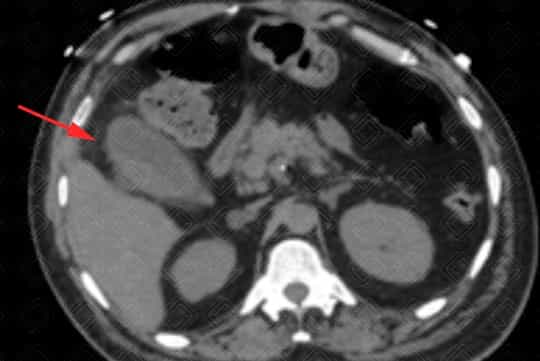

Descrição das figuras: Tomografia computadorizada de abdome com contraste venoso. Vesícula biliar contendo cálculo no seu interior, distendida, com espessamento parietal e densificação dos planos adiposos perivesiculares. Achados compatíveis com colecistite aguda.

• Tomografia computadorizada do abdome : Menos sensível quando comparado à ultrassonografia. Em alguns casos pode não visualizar o cálculo biliar. No entanto é excelente para a avaliação da inflamação perivesicular adjacente;